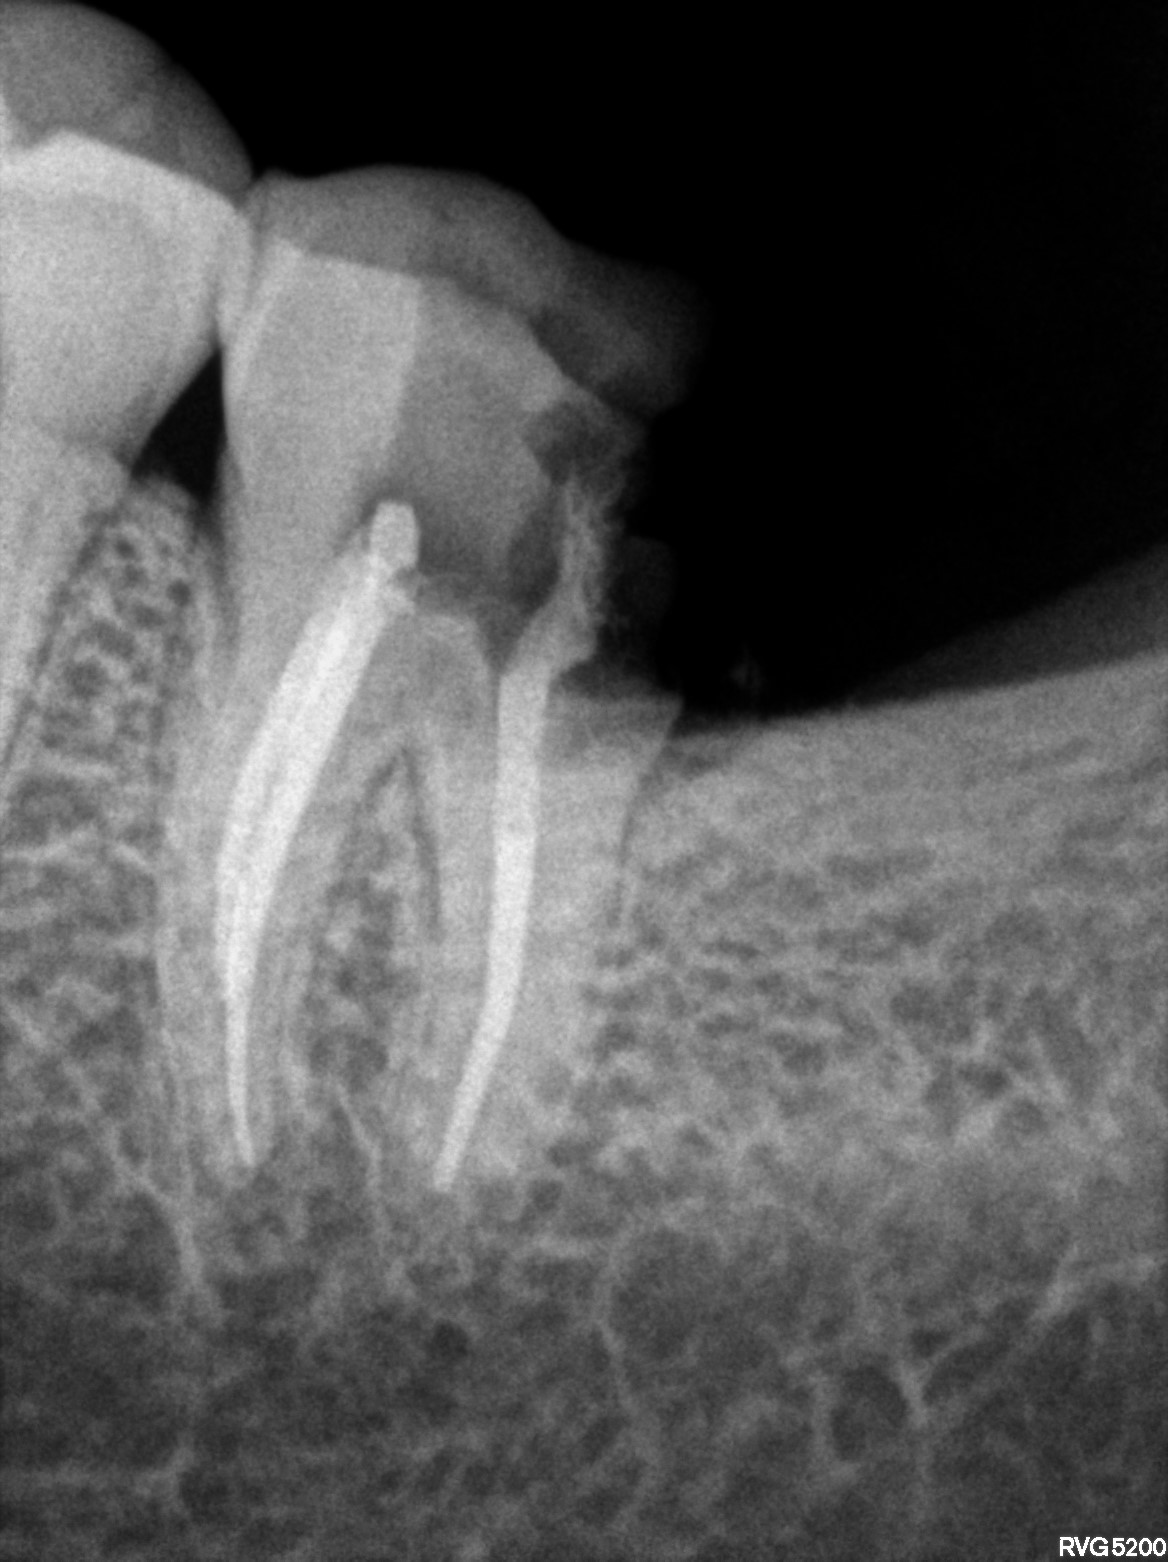

Dental Radiographs FHIR: DocumentReference · LOINC 24641-7

FHIR Bundle

R55.jpg

24641-7